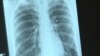

عزیزي: کندهار کې د نري رنځ ۲۶۲۸ پېښې ثبت شوي

د کندهار عامې روغتيا ریاست مسؤلين په دغه ولايت کې د نري رنځ یا توبرکلوز د ناروغيو د زياتوالي په اړه اندېښمن دي.

د کندهار د عامې روغتيا ریاست د نري رنځ څانګې مسؤل ډاکتر فتح محمد عزیزي د سې شنبې په ورځ ازادي راډیو ته وویل چې تېر کال په ښار او ولسوالیو کې د نري رنځ د ناروغۍ د تشخیص لپاره د دې ناروغۍ د درملنې ټولو روغتیايي مرکزونو ته ۱۶ زره ۴۶۰ تنه معرفي شوي چې له دې جملې څخه د ۲۶۲۸ کسانو ناروغي ثبت شوې.

د ښاغلي عزیزي په وینا د دې ناروغۍ د مخنيوي په برخه کې د دوی زیات کار هم ګټه نه‌ده کړې او د دغې ناروغۍ کچه نه‌ده کمه شوې.

نوموړي د دې ناروغۍ د کچې د لوړوالي لامل په دې ولایت کې د روغتیا په برخه کې د عامه پوهاوي د سطحې ټيټوالی په ګوته کوي.

چارواکي وايي چې د ښار په ګډون په ټولو ولسوالیو کې د دغې ناروغۍ د تشخیص او تداوي امکانات په واک لري چې په خبره‌یې هره ورځ د دغو ناروغانو درملنه په وړیا ډول کېږي.

د کندهار د عامې روغتیا ریاست د توبرکلوز څانګې متخصص ډاکتر روح‌الله پر خلکو غږ کوي چې د توبرکلوز ناروغۍ د علایمو پر مهال چې دوه اوونۍ دوامداره ټوخی دی د دوی روغتیایي مرکزونو ته مراجعه وکړي تر څو ژر تر ژره‌يې درمنله وشي.

روغتیا پالان د نري رنځ یا توبرکلوز نښې نېښانې د دوو اوونيو څخه زيات ټوخى د وزن کموالى او بې‌اشتهايي يادوي چي په وینا یې بايد په داسې حالاتو کې ناروغ سمدستي نېږدې روغتیايي مرکز ته مراجعه وکړي.